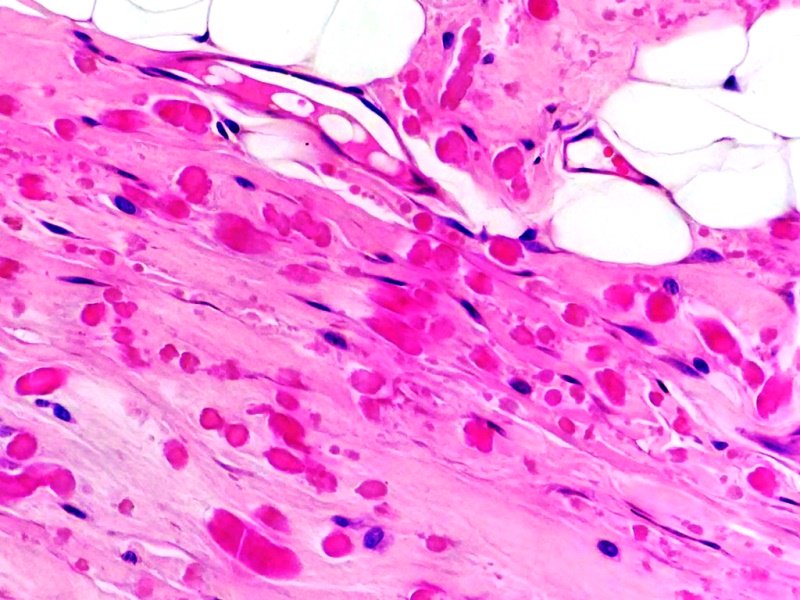

Primer artejo de pie izquierdo. Melanoma subungueal. Tinción HE